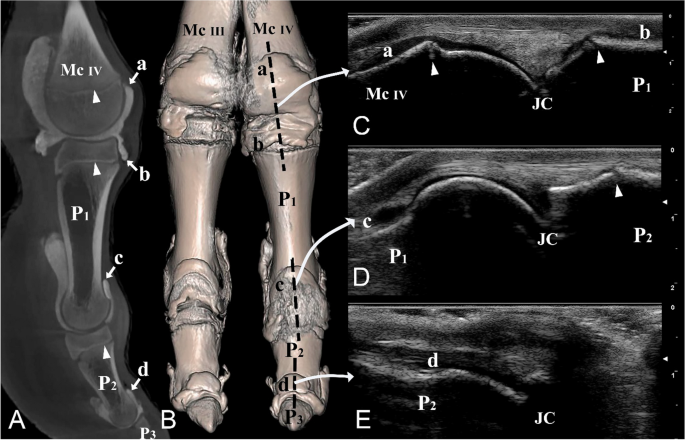

Dorsal and lateral views of the left distal forelimb and digit IV. (A) Sagittal plane CT image; (B) three-dimensional reconstruction (the black dotted line indicating the dorsal placement of the ultrasound probe), (C) longitudinal dorsal ultrasound image of the metacarpophalangeal joint, (D) longitudinal dorsal ultrasound image of the proximal interphalangeal joint, and (E) longitudinal dorsal ultrasound image of the distal interphalangeal joint. Mc III distal end of metacarpal bone III, Mc IV distal end of metacarpal bone IV, P1 proximal phalanx, P2 middle phalanx, P3 distal phalanx, a proximal dorsal recess of the metacarpophalangeal joint, b distal dorsal recess of the metacarpophalangeal joint, c proximal dorsal recess of the proximal interphalangeal joint, d proximal dorsal recess of the distal interphalangeal joint, JC joint cavity. White arrowheads indicate the epiphyseal lines.

The ultrasonographic images revealed that the tendons and other soft tissues surrounding the joint cavities appeared hyperechoic. In contrast, the synovial fluid within the joint cavities demonstrated hypoechoic characteristics. The digit joints were examined with ultrasonography from a dorsal, lateral, and palmar/plantar aspect, in an extended position (Figs. 3C, 5C–E, 6C,D, 7C). The epiphyseal lines of the distal ends of the metacarpal and metatarsal bones and the proximal ends of P1 and P2 were distinguished (Figs. 3C, 5C,D, 6C,D). Furthermore, the joint cavities of the metacarpophalangeal, metatarsophalangeal, proximal interphalangeal, and distal interphalangeal joints were identified via the dorsal aspect (Fig. 5C–E). P3 could not be viewed via the dorsal aspect because of the obstruction of the hoof capsule.

On the lateral aspect of the digit, our observations included the distal end of the metacarpal/metatarsal bones, the metacarpophalangeal/metatarsophalangeal joint cavities, P1, proximal interphalangeal joint cavities, and P2 (Fig. 6C,D). Furthermore, the large palmar/plantar pouches of the metacarpophalangeal/metatarsophalangeal and proximal interphalangeal joints were identified (Fig. 6C,D).

Computed tomography

The CT scans in this study provided three-dimensional images with exceptional detail, allowing for a clear visualization of the distal limb including joint cavities, recesses, and pouches of the metacarpophalangeal/metatarsophalangeal joints, as well as the proximal and distal interphalangeal joints (Figs. 3A,B, 5A,B, 6A,B, 7A,B). The CT results were in accordance with the ultrasound findings, supporting the accuracy of our anatomical observations.